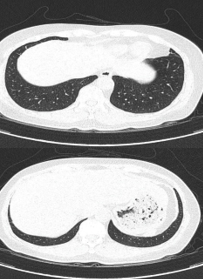

– Cắt lớp vi tính lồng ngực: Đám xẹp vùng đỉnh phổi phải, nốt đặc nhỏ kích thước 2-3mm. Không thấy hạch to hay khối trong trung thất

Hình 10: Hình ảnh cắt lớp vi tính ngực có tiêm: Đám xẹp vùng đỉnh phổi phải, nốt đặc nhỏ kích thước 2-3mm

Hình 11: Hình ảnh cắt lớp vi tính ngực có tiêm: Không thấy hạch to hay khối trong trung thất